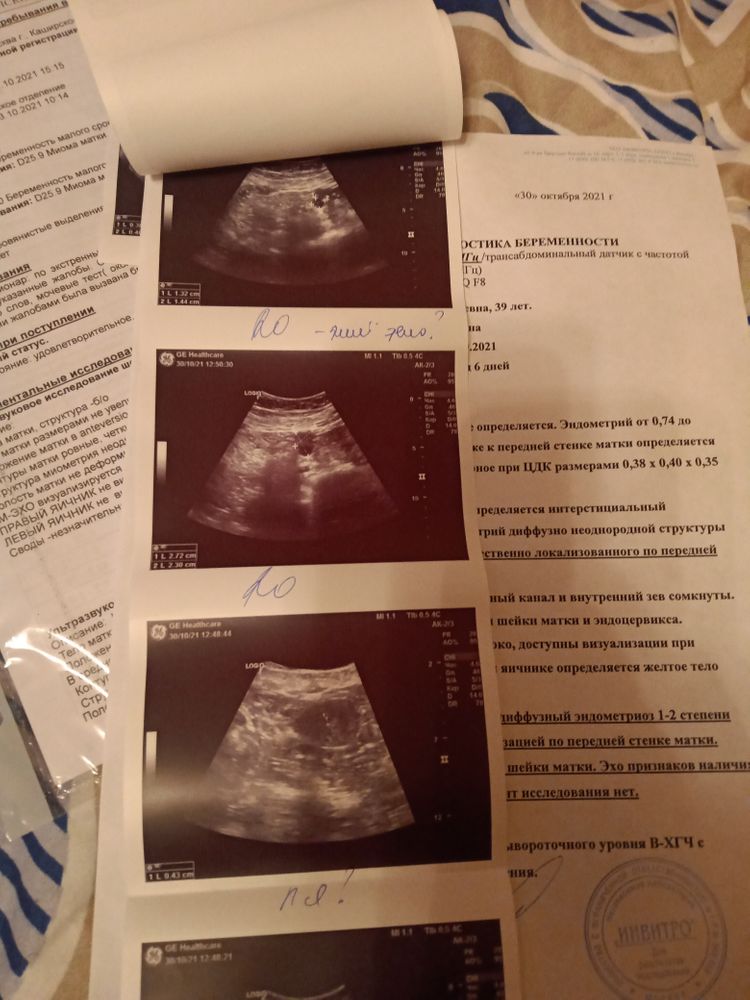

Извелась уже вся,на УЗИ ничего не видят не в матке не в трубах, настаивают на госпитализацию с подозрением на внематочную!!!!Я больше не могу об этом думать,врачи отправляют в больницу,все в один голос утверждают,что внематочная,А я не верю,надеюсь на лучшее!!!Следующий ХГЧ сдам 11,11,а 12,11 пойду к врачу,уж точно что то должно показаться!!!

Катя, Я делала в Инвитро платно,вроде есть ПЯ,а вроде нет

Татьяна Ерошкина, надо сделать узи в месте, где специализируются на узи по беременности. Они плодное яйцо под вопросом ставят. Вы 30 октября делали узи, я бы завтра сходила переделала, оно бы подросло и картина уже более понятная бы была.

Катя, Я сегодня делала в ЖК,и они меня пугают внематочной,а на это УЗИ,даже внимание не обращают,говорят там нет ничего,а под вопросом это вроде правый яичник написано,ну и там же пишут плодное яйцо, ничего не понятно